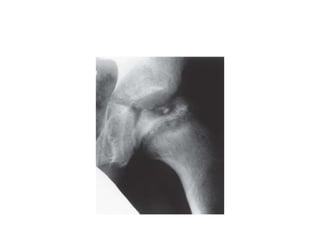

• HINGE ABDUCTION

• described by Grossbard in 1980

-IMPINGEMENT OF THE OUTER PART OF

FEMORAL HEAD ONTO THE LATERAL LIP OF

ACETABULUM

• sudden deterioration of ROM during follow up

• reducible and irreducible type

• DIAGNOSED by arthrography or dynamic MRI